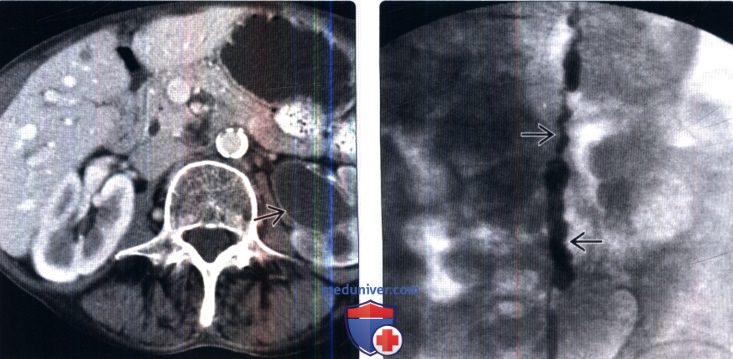

Изображения КТ конкрементов мочевого пузыря